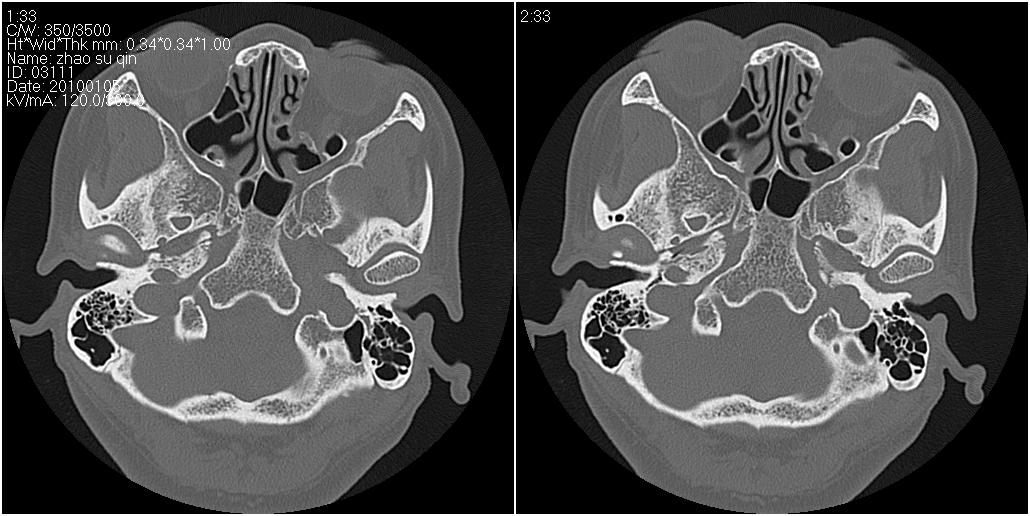

标题: CT24015:一个头部外伤患者进行鉴定,除了左侧筛板骨折,哪 [打印本页]

标题: CT24015:一个头部外伤患者进行鉴定,除了左侧筛板骨折,哪

看了几遍,其余未见明显骨折征。

左眶下裂部好像有骨折 似有小碎骨片

1)左侧筛板骨折。2)双侧筛窦炎症(或积血)。

其余未见明显骨折征。

请明示骨折部位。